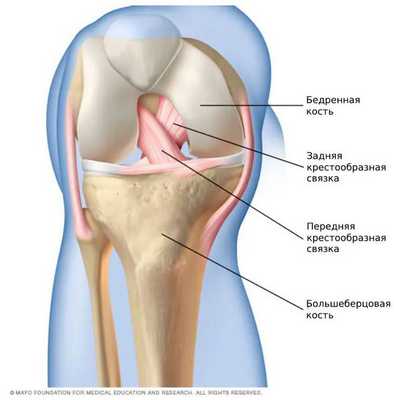

Передняя крестообразная связка состоит из спирально расположенных коллагеновых волокон, которые обеспечивают её прочность и растяжимость [7] [10] . Своим верхним концом ПКС прикрепляется к бедренной кости, а нижним — к большеберцовой. На середине хода ПКС пересекается с задней крестообразной связкой. И з-за характерного перекрёста данные связки и получили своё название [8] [9] .

![Передняя и задняя крестообразные связки [15]](/pimg3/priznaki-vertikalnogo-prodolnogo-9DFD.jpg)